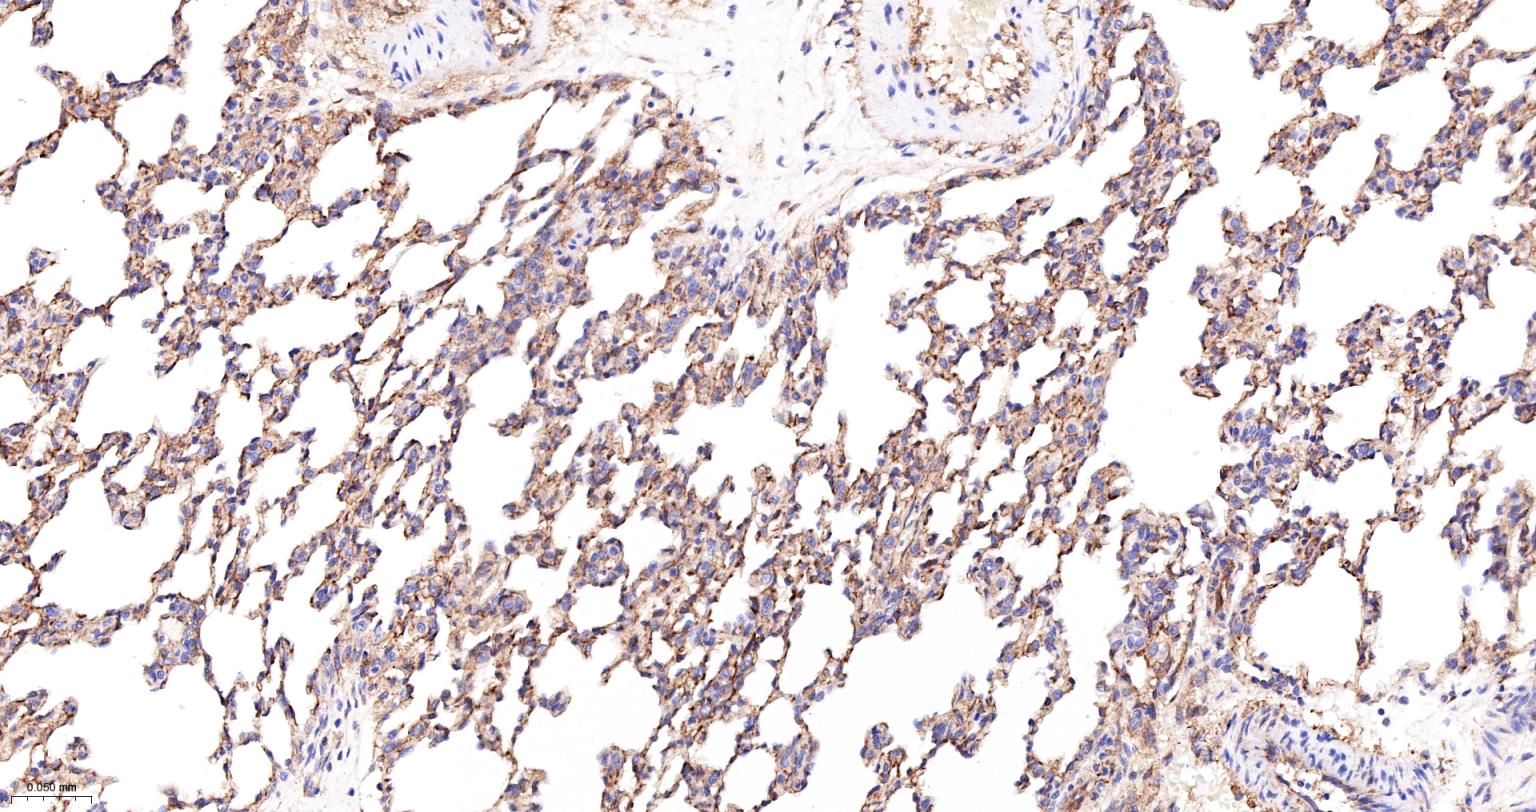

Paraformaldehyde-fixed, paraffin embedded Rat Lung; Antigen retrieval by boiling in sodium citrate buffer (pH6.0) for 15 min; The section was incubated with Radixin Monoclonal Antibody, Unconjugated (bsm-61253R) at 1:200 overnight at 4°C, followed by conjugation to the bs-0295G-HRP and DAB (C-0010) staining.

Paraformaldehyde-fixed, paraffin embedded Mouse Lung; Antigen retrieval by boiling in sodium citrate buffer (pH6.0) for 15 min; The section was incubated with Radixin Monoclonal Antibody, Unconjugated (bsm-61253R) at 1:200 overnight at 4°C, followed by conjugation to the bs-0295G-HRP and DAB (C-0010) staining.